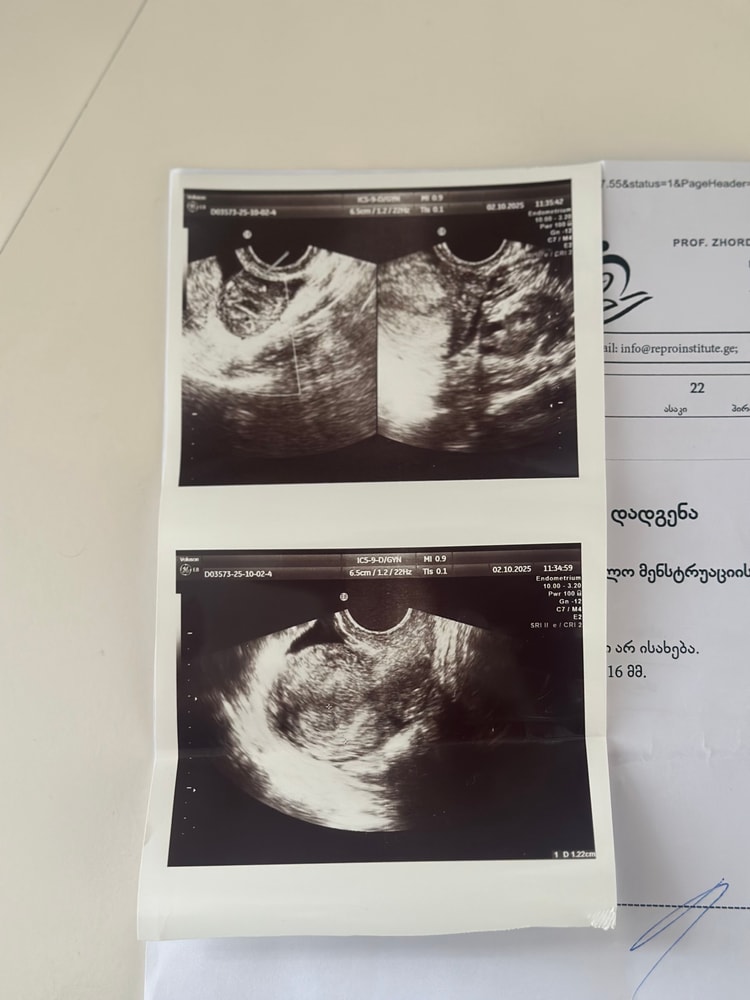

Подскажите пожалуйста может кто то разбирается? Хгч 2258 , но сказали на узи ничего нет переживаю очень

Елизавета , еще хгч очень быстро растет , 30 числа 580 был, а 2 числа 2258, Незнаю тоже это что из за чего так быстро растет